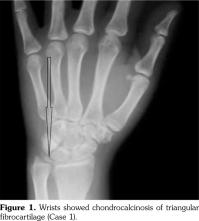

Case 2- A 39-year-old male patient presented with swelling of both knee joints. He also gave a history of recurrent painful swelling of knee joints and wrist joints for more than 10 years and was treated by an Ayurvedic physician. Other medical history or family history of medical problems were insignificant. There was a massive swelling of both knee joints with effusions, which was aspirated and the X-rays revealed calcification of the articular cartilages (Figure 5). A written informed consent was obtained from the patient.

His hand X-rays showed hook like projections arising from radial aspect of second and third metacarpal heads with scapholunate advanced collapse and indentation of distal radius by the scaphoid bone. It also showed CC of the triangular fibrocartilage (Figure 6).

He had chondrocalcinosis involving the menisci and hyaline cartilage, with predominant patellofemoral joint osteoarthritis. His blood investigations to find a metabolic cause for CC were negative.